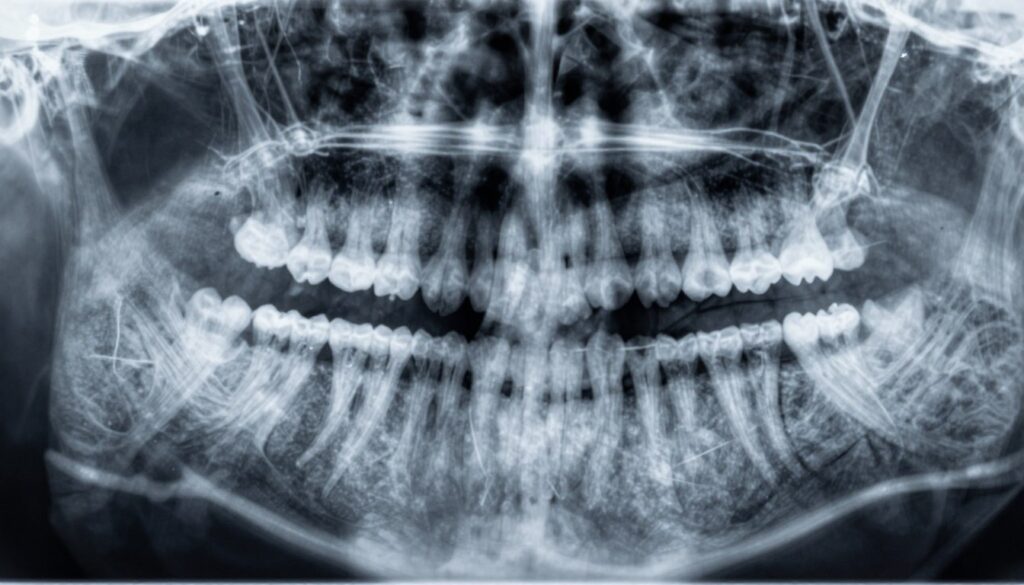

Pantomogram obejmuje cały łuk i służy do oceny ogólnej: ósme zęby, relacje łuków i struktury kości. To pierwsze badanie przy planowaniu większych zabiegów.

Co oznaczają cienie na zdjęciu RTG zęba

Cienie na obrazie bywają mylące; warto poznać podstawowe reguły ich interpretacji.

Ciemne obszary zwykle oznaczają większą przenikalność dla promieniowania — to mogą być przestrzenie z powietrzem, płynem lub ubytek mineralizacji. Jaśniejsze pola wskazują na gęstsze struktury, jak wypełnienia, korony czy zwarta kość.

Nie każdy cień to zmiana patologiczna. Czasem to rzut zatoki, kanału żuchwy lub nakładanie się struktur. Lokalizacja i kształt pomagają rozróżnić anatomiczne rzutowania od realnej zmiany.

Zmiany zapalne w kości często pojawiają się wokół wierzchołka korzenia. Mogą wyglądać jak przejaśnienia o różnym kształcie i wielkości. Niekiedy pacjent ma niewielkie dolegliwości, mimo wyraźnej zmiany na obrazie.

Porównanie zdjęć w czasie jest kluczowe. Stabilny cień zwykle nie wymaga natychmiastowego leczenia. Powiększający się obszar sugeruje konieczność dalszej diagnostyki, często w 3D.